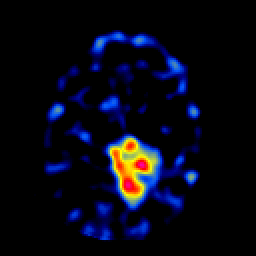

SPECT TL Study #6 -- Slice #38

[Home][Help][Clinical][Tour 1][Tour 2][Tour 3] Slice 38